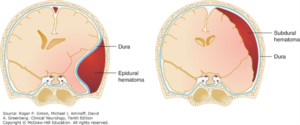

• The meningeal spaces in the cranial cavity are only present between the periosteum and dura (epidural) and dura and arachnoid (subdural) in pathological conditions, like hematomas or hemorrhages. Otherwise these two meningeal spaces are “potential.”

• Figure 2.4. Hematoma into the meningeal spaces. Confusional States, Simon RP, Aminoff MJ, Greenberg DA. Clinical Neurology, 10e; 2017. Accessed July 17, 2018.

Bleeding from a rupture of meningeal vessels passes into the epidural space, an epidural hematoma. Bleeding associated with the cerebral veins can pass into the subdural space, a subdural hematoma. (See Figure 2.4.)

• Both epidural and subdural hematoma have distinct radiographic signs. An epidural hematoma is lens-shaped and restricted by the sutural attachments of the dura mater and a subdural hematoma is crescent-shaped following the convexity of the cerebral hemisphere. (See Figure 2.4.)

Both epidural and subdural hematomas also lead to increases in intracranial pressure.